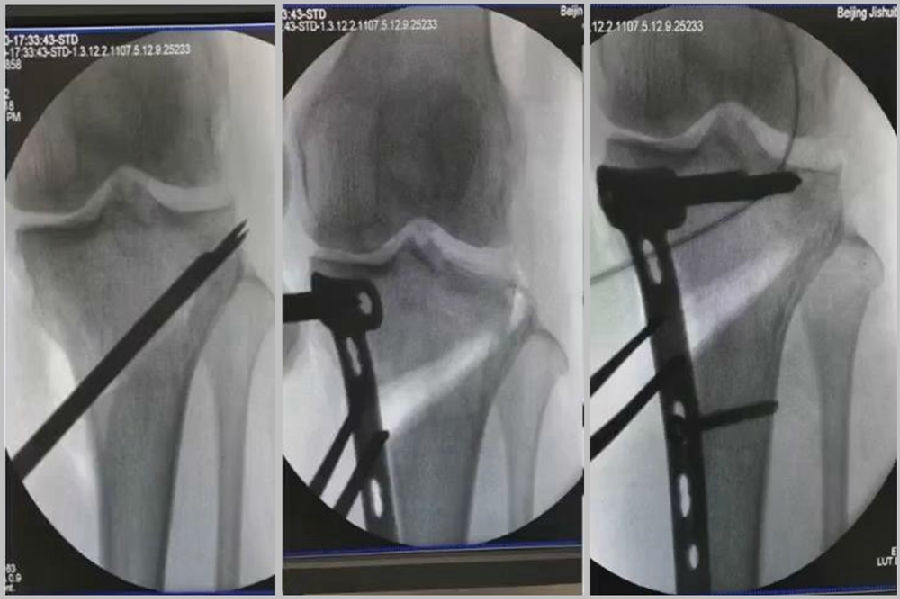

2、处理

(1)如果在手术台上,或是刚做完手术就发现矫正不良问题,此时比较简单。需要先跟患者进行沟通,在手术中直接将远端4颗螺钉卸下来,调整好力线后重新打入即可。但是注意要把远端单皮质螺钉换成双皮质螺钉。

(2)如果患者已经达到初始愈合,此时如果出现过度外翻,需要在内侧重新做内侧闭合楔。

(3)如果做完手术时间较长,出现过度矫正或矫正不足时,需要重新做力线分析,看一看力线在哪个方向可以再进行调整。胫骨侧有调整余地,就在胫骨侧进行调整;股骨侧需要调整,就在股骨侧进行调整。